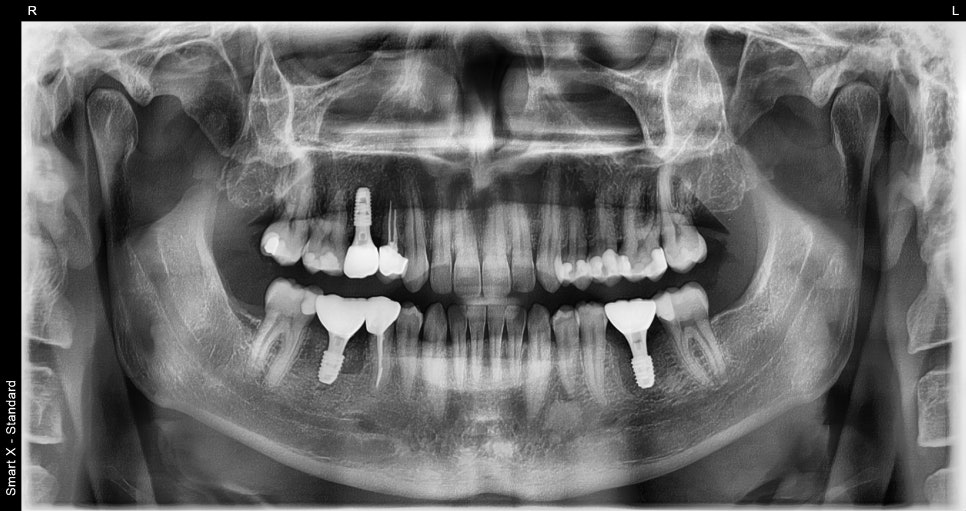

오래전 해외에서 치료 후 통증을 호소하며 내원하신 환자분 초진 파노라마 엑스레이 입니다.

오른쪽 아래 첫번째 큰 어금니는 뿌리끝 염증이 심했고, 좌측 첫번째 큰 어금니는 충치가 심해 머리부분 파절이 관찰되었습니다.

임플란트 식립 후 촬영한 파노라마 엑스레이입니다.

양 옆 치아와 똑같이 가지런히 잘 식립되어 있습니다.

임플란트가 안정적으로 유착된 후, 보철물을 장착 완료 된 최종 파노라마 엑스레이입니다.